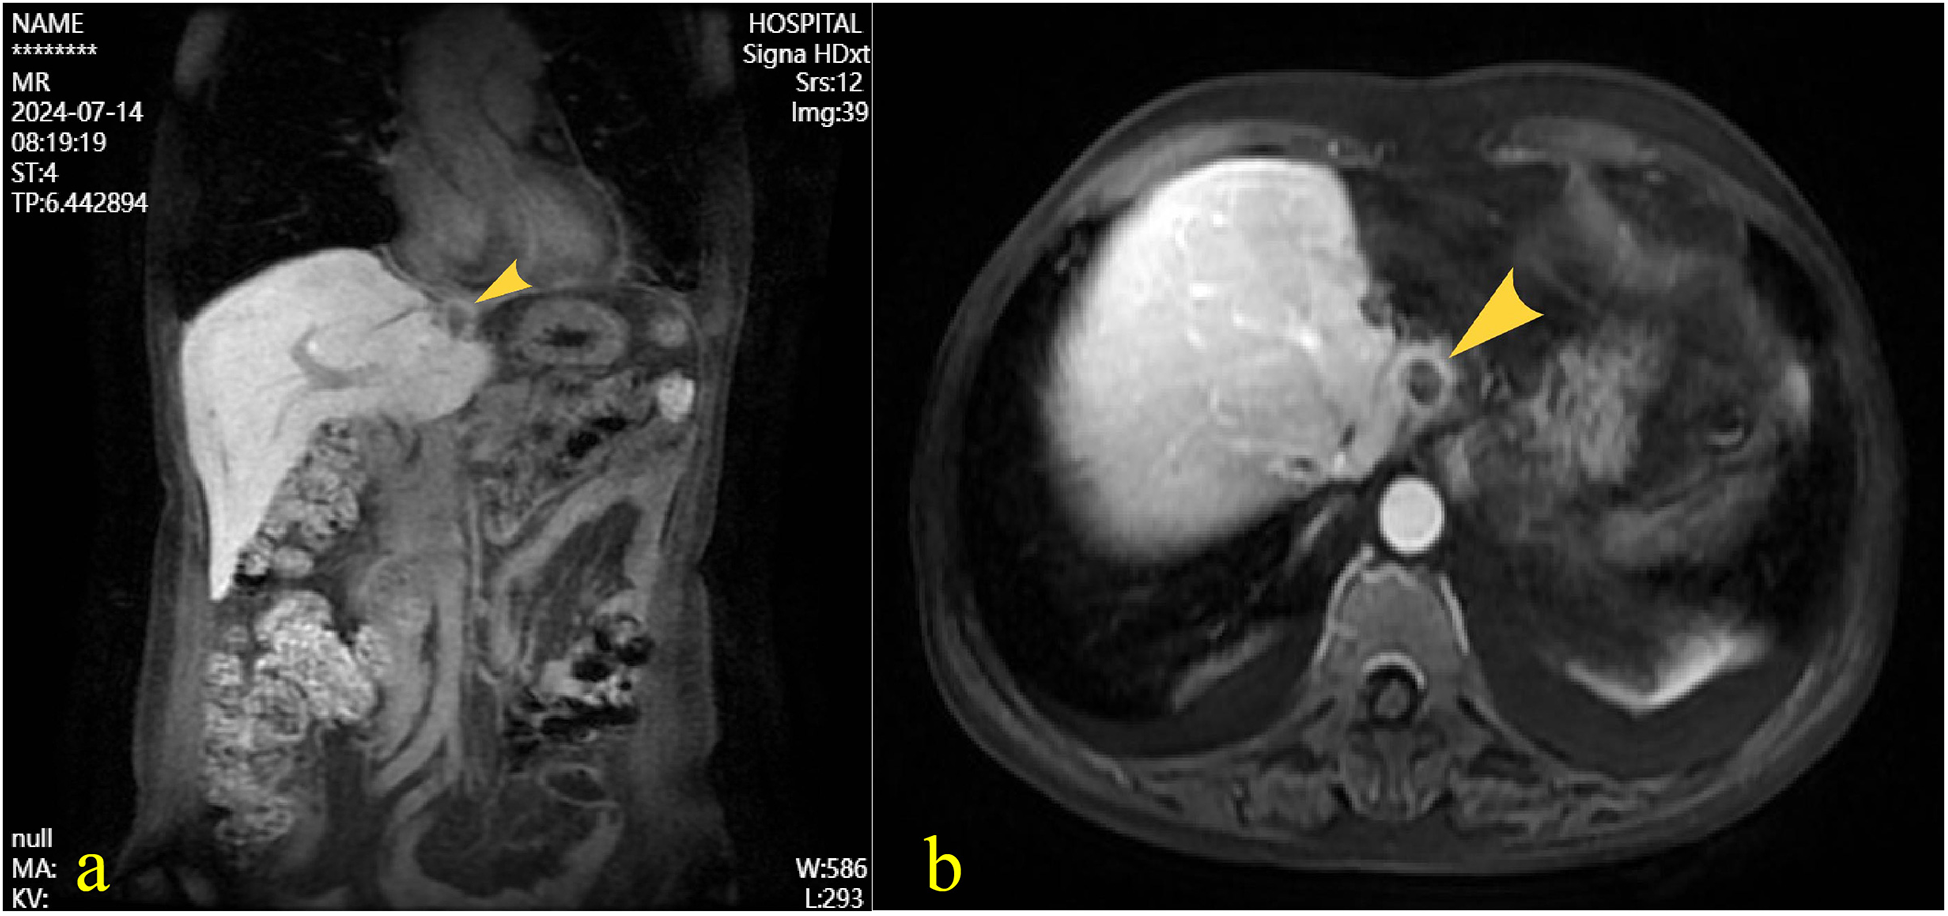

A 55-year-old female patient with a 2-week history of bilateral lower extremity edema was admitted to our department (July 4, 2024), who had a history of left liver lobectomy for intrahepatic bile duct stones. Laboratory tests on admission showed that the alpha-fetoprotein (AFP) value was 225 times higher than the upper limit of the normal reference range (0–15 ug/L), and the carbohydrate antigen (CA125) value was 9 times higher than the upper limit of the normal reference range (0–20 U/mL). Large amounts of pericardial effusion were seen on cardiac ultrasonography. Following the evacuation of the effusion, a faint echogenic mass of approximately 4.4 × 2.5 cm was observed in the pericardial cavity near the bottom of the right heart. (Figure 1a, July 22, 2024). And, an enhanced computed tomography (CT) revealed an intrapericardial mass measuring around 4.0 × 2.1 cm and a right pleural effusion, but no liver mass was detected (Figure 1b, July 6, 2024). Subsequently, the systemic positron emission tomography (PET) examination showed an abnormal uptake of 18-fluoro-2-deoxyglucose in the areas of the upper margin of the hepatic caudate lobe, the right margin of the heart and the banded soft tissue beside the ascending aorta (Figure 2, July 11, 2024). Utilizing hepatobiliary specific magnetic resonance contrast agents in enhanced magnetic resonance imaging (MRI), we discovered a circular enhancement in the left hepatic lobe close to the diaphragm surface with a diameter of 0.6 cm (Figure 3, July 14, 2024). Piercing fluids from both pericardial and thoracic cavities were bloody exudate, and no malignant cells were detected. On July 24th, 2024, surgical exploration was performed and an irregular and sessile fish-fleshed-like soft tissue mass in the pericardium near the bottom of the heart was found, measuring approximately 4 cm × 5 cm. Meanwhile, a tissue with a size of about 8 cm*7.2 cm*1.6 cm was removed during the operation, and a cardiac malignant tumor was identified by pathological biopsy. The immunohistochemistry results indicated a metastatic hepatic adenocarcinoma or metastasis of hepatocellular carcinoma (Figure 4). During surgical exploration the mass was found not to invade the myocardium but demonstrated ill-defined margins with the diaphragm. Subsequent diaphragmatic incision revealed an intact hepatic surface, suggesting low probability of direct hepatocellular carcinoma extension to the heart. Intraoperative identification of multiple soft tissue masses in the pericardial transverse and oblique sinuses prompted cytoreductive surgery for widespread metastases. Postoperative therapy with Lenvatinib combined with camrelizumab was initiated. During monthly outpatient follow-ups, serially elevated AFP levels reaching 7,920 times the upper reference limit were observed (Supplementary Data Figure S1). Surveillance CT demonstrated progressive massive pleural effusion with newly developed thoracic and abdominal cavity metastases. The patient received palliative care and died on January 3, 2025.

Figure 3

Following intravenous administration of gadoxetate disodium, magnetic resonance imaging of the liver revealed a well-defined roundish abnormal signal near the diaphragmatic surface of the left hepatic lobe. The lesion demonstrated mixed iso-to-hyperintensity on T1-weighted imaging, with signal drop-out on opposed-phase sequences, and iso-to-hyperintense signal on T2-weighted imaging. The longest diameter measured approximately 1.2 cm. (a) coronal view, (b) Axial view.